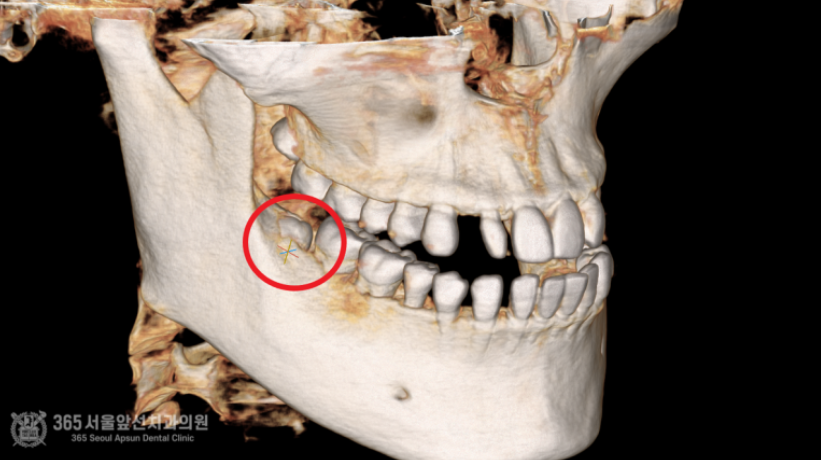

안녕하세요. 주안동치과 365서울앞선치과의원입니다. 하루에도 몇 건씩 사랑니가 불편하셔서 오시는 환자분들을 만나뵙고 있습니다. 환자분들께 치과에 대한 안좋은 기억을 여쭤보면 항상 빠지지않고 나오는 이야기가 바로 사랑니 발치인데요~ 그만큼 많은 환자분들께서 사랑니로 인해 불편감을 호소하고 계시고 발치도 많이 하고 가십니다. 하루에도 몇 건씩 발치를 하다보니 밥먹듯이 하는 진료가 되어버렸네요 ㅎㅎ 촬영일시 : 2024.06.25. 내원 당시 파노라마 엑스레이 사진 입니다. 간단한 사랑니 발치부터 완전 매복 사랑니까지 매일매일 다양한 사랑니 환자분들께서 찾아오십니다. 최근에 오셨던 환자분인신데요. 위와 아래 사랑니가 모두 매복된 형태를 보이고 있습니다. 매일매일 완전매복 사랑니 발치를 시행하고 있기에 매복 사랑니는 대수로운 문제가 아니지만 해당 환자분께서는 조금 특이한 양상이 있어서 포스팅을 하게 되었습니다. 사진 상 빨간색 동그라미 친 아래부분 사랑니의 경우 사랑니의 머리가 설측(혀쪽)으로 향하고 있는데요. 사랑니를 발치할때 기구 접근이 사랑니의 머리쪽으로 이루어져야 하므로, 사랑니 머리가 협측(볼쪽)으로 나와있는 것이 발치에 유리합니다. 즉, 해당 환자분은 사랑니발치 난이도가 꽤 높은 편 에 해당하는 특이한 형태였습니다. 촬영일시 : 2024.06.25. 내원 당시 CT 사진 : 아래쪽 사랑니가 뼈에 거의 묻혀있고 사랑니의 머리가 혀쪽으로 기울어져있는 것이 보입니다. 쉽지 않아보이네요. 촬영일시 : 2024.06.25. 여러 각도에서 CT 분석을 시행합니다. 비록 난이도가 높은 사랑니 발치에 해당했으나, 위아래 사랑니 모두 발치하는 것부터 봉합하는데 걸린 시간까지 총 12분이 걸렸고 환자분께서는 빠르고 정확한 발치에 만족하시며 귀가하셨습니다 ^^ (지혈 거즈를 물고 계셔서 비록 말씀은 못하셨으나 왼쪽 손으로 엄지척 해주셔서 뿌듯했습니다 ㅎㅎ) 촬영일시 : 2024.06.25. 안전하게 발치가 완료된 파노라마 엑스레이 사진입니다. 매일 사랑니 발치와 관련하여 다양한 환자분들을 만나뵙고 있는데요. 환자분들의 고통을 해결해드리고, 치료에 만족하시는 모습을 볼때마다 치과의사로서의 삶에 하루하루 뿌듯함을 느낍니다. 지금까지 365일 열린 가까운 서울대학교 치과병원을 지향하는 365서울앞선치과였습니다. 감사합니다. [ 치료기간: 2024년 6월25일 ] ※ 365서울앞선치과의원의 모든 포스팅은 각 진료과 의료진이 직접 작성합니다. 365서울앞선치과의원 블로그의 임상 케이스 게시물은 환자분께 의학적으로 정확하고 상세한 정보를 드리기 위해 각 진료과 의료진이 직접 작성하며, 모든 증례 사진은 본원 의료진이 직접 시술한 증례를 촬영한 것으로, 의료법 제23조, 제56조에 의거하며 환자분의 동의를 얻어 포스팅에 사용하였습니다. 또한 해당 케이스는 본 환자분의 치료 결과이며, 환자 상태에 따라 치료의 결과는 달라질 수 있습니다. |